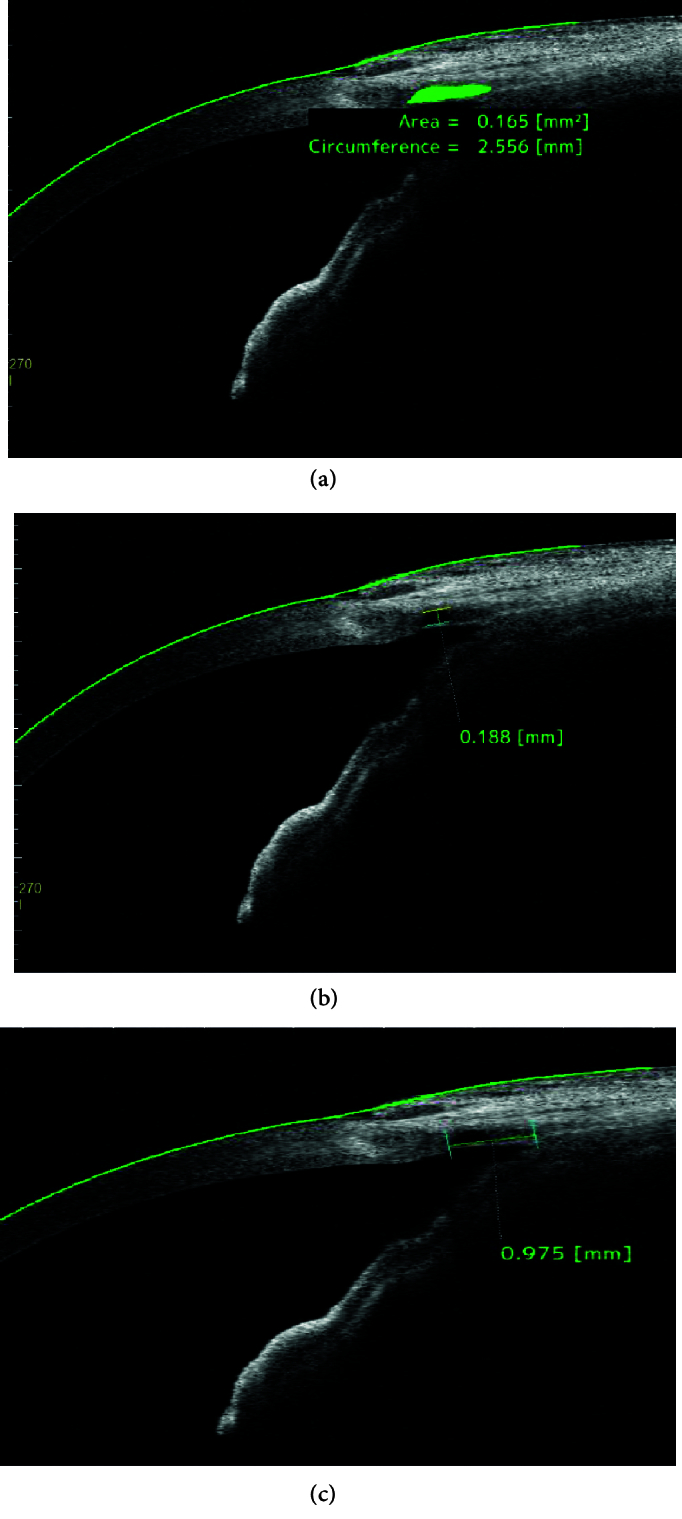

Methods: In total, 36 eyes with POAG eligible for phaco-VC were enrolled in this prospective observational study. All patients underwent AS-OCT evaluation and ophthalmologic examination including Goldman tonometry, cup-disc ratio assessment, best corrected visual acuity (BCVA) measurement, and antiglaucoma medication(s) prior to surgery and one, three, and six months after the surgery. The width, length, area, and circumference of the ILs were evaluated using AS-OCT at each follow-up.

Results: A total of 36 eyes of 34 patients with POAG were investigated in this study. According to the results, the mean age of the patients was 70.09 ± 8.73 years, and the majority of the cases were male (n = 23; 63.9%). The mean preoperative intraocular pressure (IOP) was 20.11 ± 7.22 mmHg on 2.47 ± 1.1 medications, and the mean postoperative IOP reduced to 11.11 ± 2.58 mmHg on 0.11 medications, which was statistically significant (P < 0.001). ILs were detectable in all cases which resulted in a 100% qualified success rate. The reduction in the width, area, and circumference of the IL was significant during the six-month follow-up. The relationship between IOP changes and IL parameters on AS-OCT was not significant.